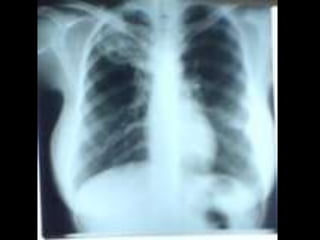

• C’est un téléthorax de face objectivant une opacité de tonalité

hydrique siégeant au niveau du champ pulmonaire inférieur

gauche, de forme ovalaire, mesurant 5cm de grand axe, de plage

hétérogène par la présence de broncho gramme, de limites plus

ou moins nettes et les contours sont irréguliers.

• En appliquant le signe de la silhouette, l’opacité n’efface pas le

bord gauche du médiastin donc elle est de topographie

postérieure. Ailleurs on note une opacité hilaire gauche

irrégulière. L’index cardio-thoracique est normal, les culs de sac

pleuraux sont libres, pas de lésions osseuses visibles.

• Conclusion : syndrome de comblement alvéolaire évoquant un

cancer broncho-pulmonaire, métastase pulmonaire unique

Diagnostic différentiel : abcès du poumon, tumeur bénigne.

• CAT : TDM thoracique, échographie abdomino-pelvienne et

scintigraphie osseuse Fibroscopie bronchique